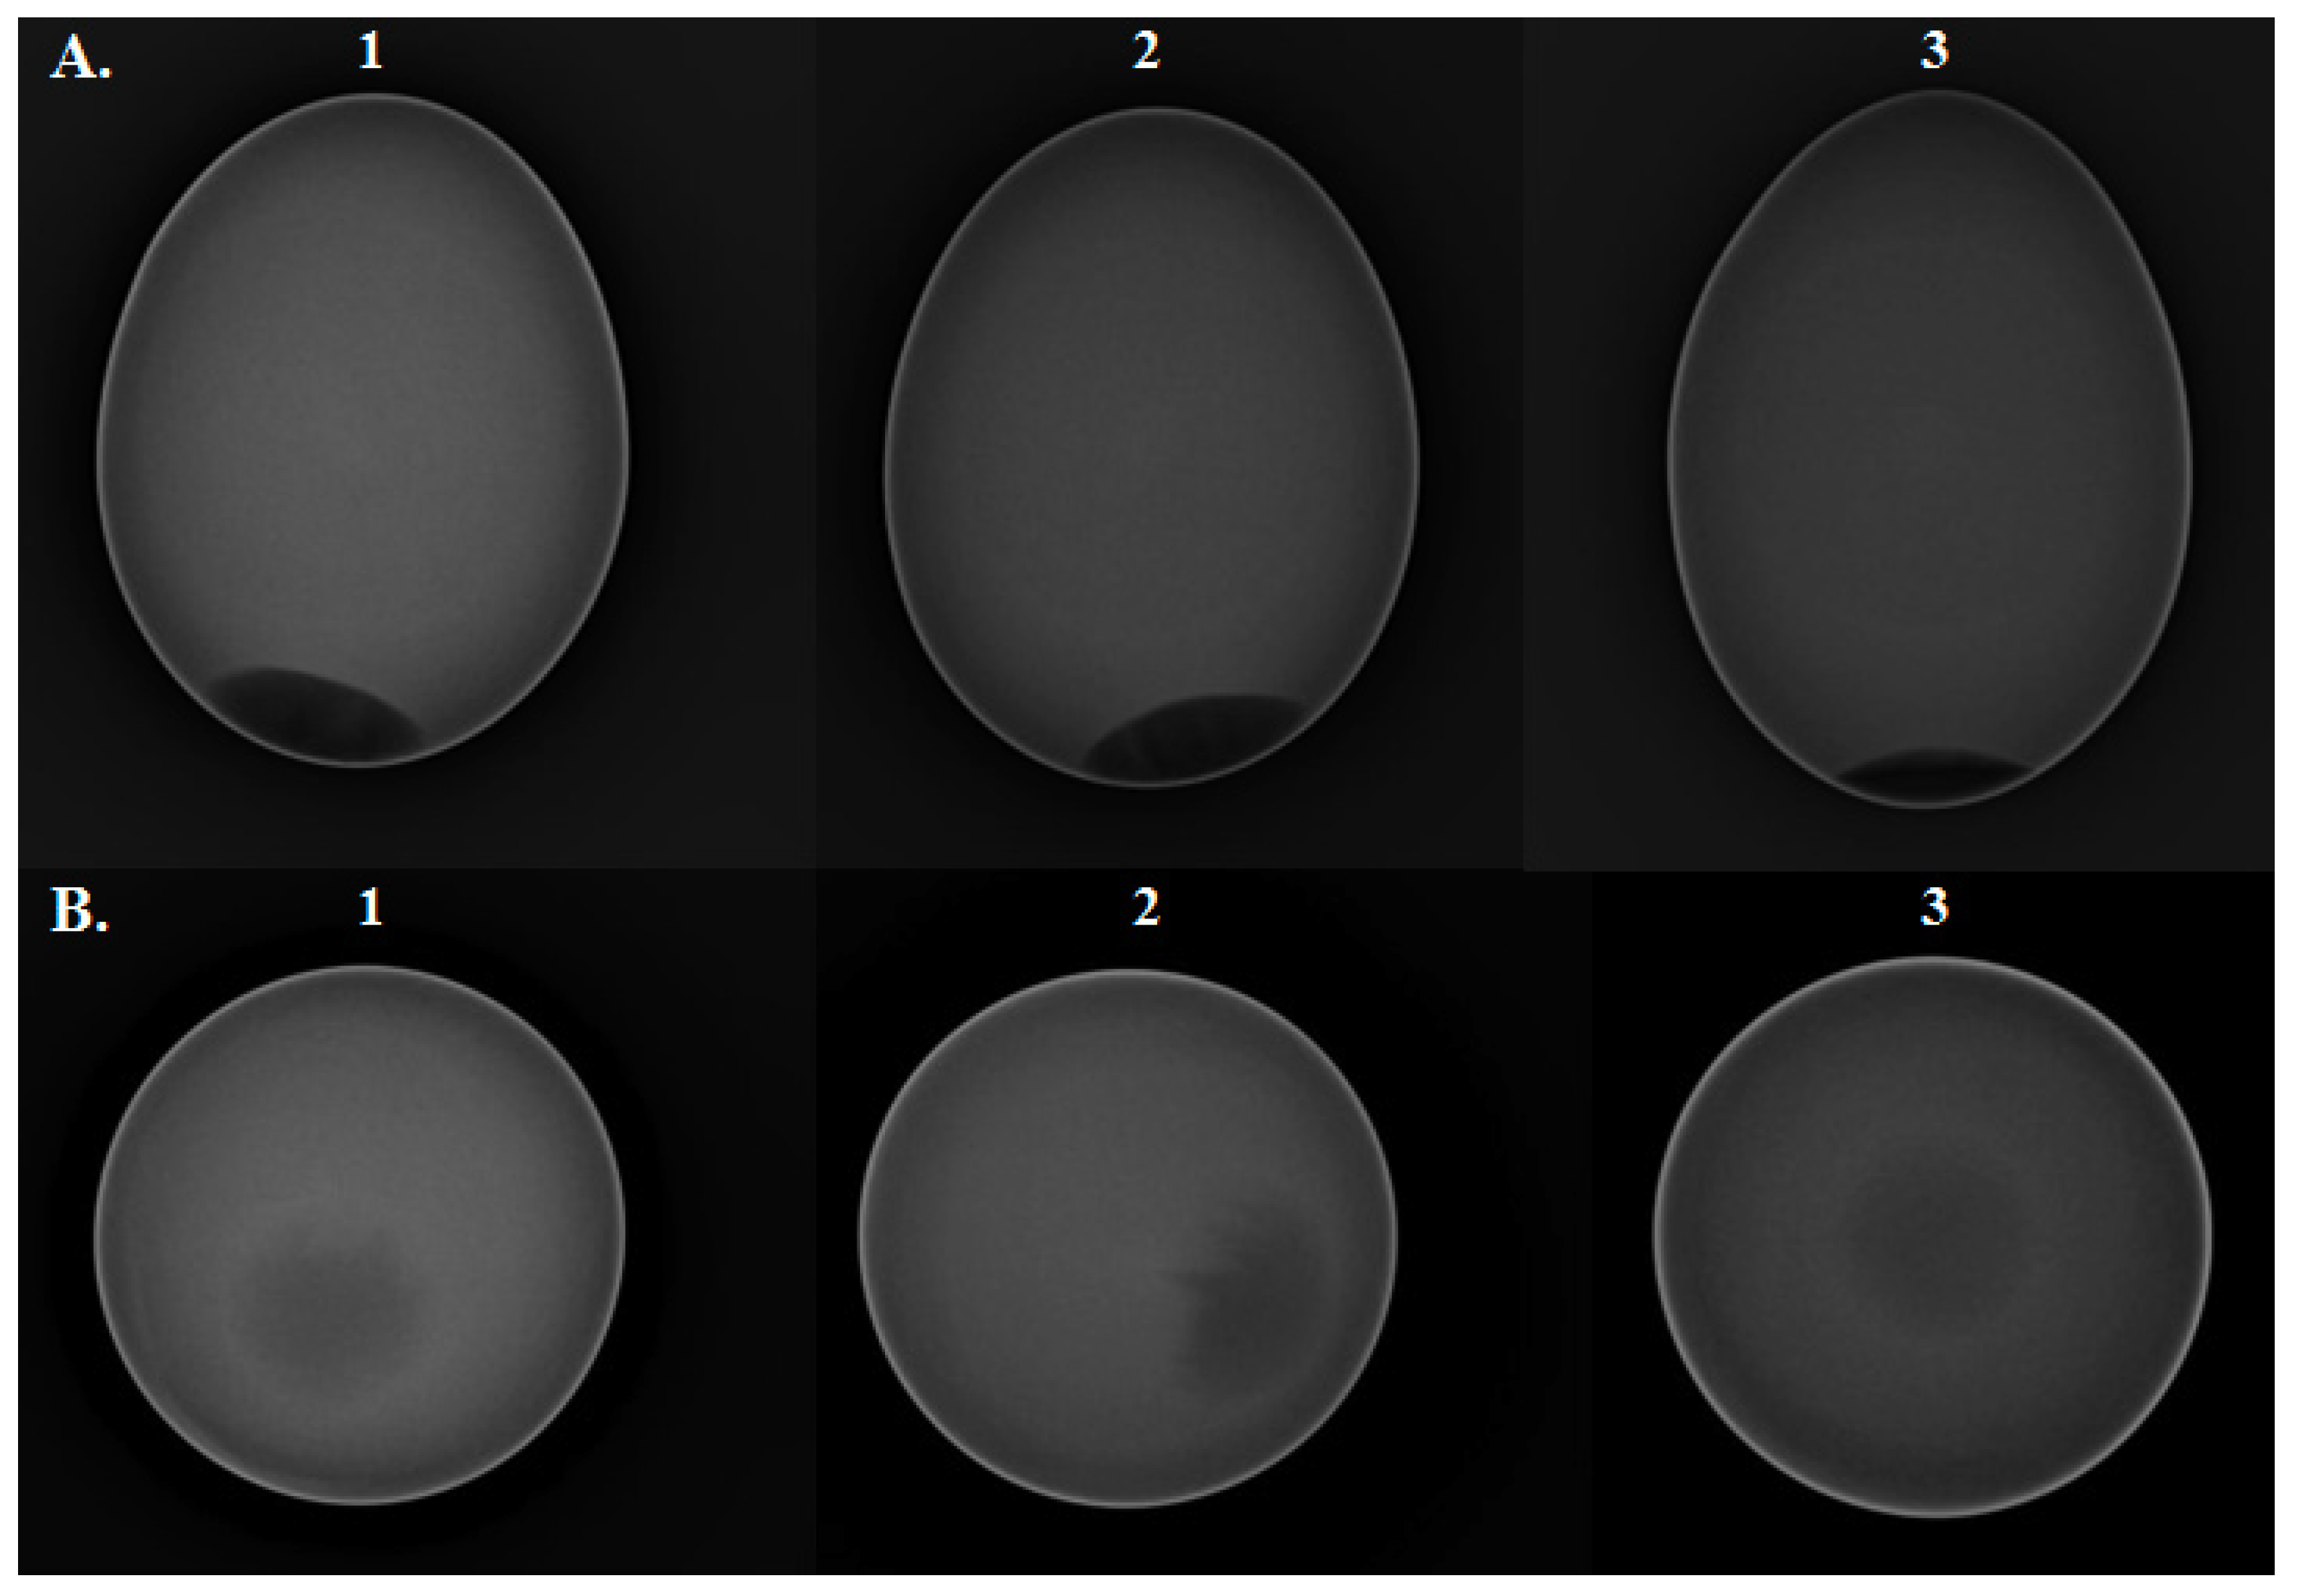

Radiographic imaging was used to create DICOM grayscale images for three eggs of different qualities. With the differences in signals between the X-ray intensity and the density of the illuminated object, as the density of the matter goes from low to high, the linear attenuation coefficient for the ionizing radiation also goes from low to high. Accordingly, the exposure effect of ionizing radiation on digital X-ray flat panel detectors (FPD) changes from strong to weak, and the rendered image gradually changes from a low-signal image (dark) to a high-signal image (bright). The results are shown in Figure 2.

Images (1), (2), and (3) in Figure 2 are the DICOM grayscale imaging of SO eggs, GO eggs, and CO eggs, respectively, where Figure 2A shows a median plane image and Figure 2B shows an axial plane image. The figure shows that the shell structure is mainly composed of calcium carbonate (CaCO3) crystals, which render it as a high-signal image (bright) in a radiographic signal. The air cell is mainly a gas structure, which renders a low-signal image (dark) in the radiographic signal. The yolk and albumen are rendered as a mid-signal image (gray). This is because the yolk and albumen are in a liquid state, which cannot have clear boundaries like the shell. The states of the yolk and albumen cannot be distinguished visually from the gray-scale images, and thus the quality of the egg cannot be distinguished. From the figure, only the difference in size of the air cell in images (1), (2), and (3) in Figure 2A can be seen.

Figure 2. Comparison of photometric interpretation of monochrome images under the Digital Imaging and Communications in Medicine (DICOM) standard for eggs of three different qualities imaged at 50 kVp and 20 mAs: (A) median and (B) axial plane images. (1) special organic (SO) eggs, (2) general organic (GO) eggs, and (3) conventional (CO) eggs.

Figure 2, Figure 3 and Figure 4 show the corresponding results of radiometric DICOM gray-scale imaging and stratification analysis of the visualization. The DICOM gray-scale image in Figure 2A corresponds to the result of the stratification analysis of the visualization in Figure 3. The DICOM gray-scale image in Figure 2B corresponds to the result of the stratification analysis of the visualization in Figure 4. For both pairs, there is no significant visual difference in the DICOM gray-scale images. However, in the stratification analysis of visualization, there are indeed some visual differences in the imaging between the inner egg in Figure 3A,C. The quality and freshness still cannot be determined based on the visual differences. To clearly analyze the results, a one-way ANOVA was conducted on the data visualization statistics for a scientific statistical comparison of the egg quality and freshness. The results are shown in Figure 5.